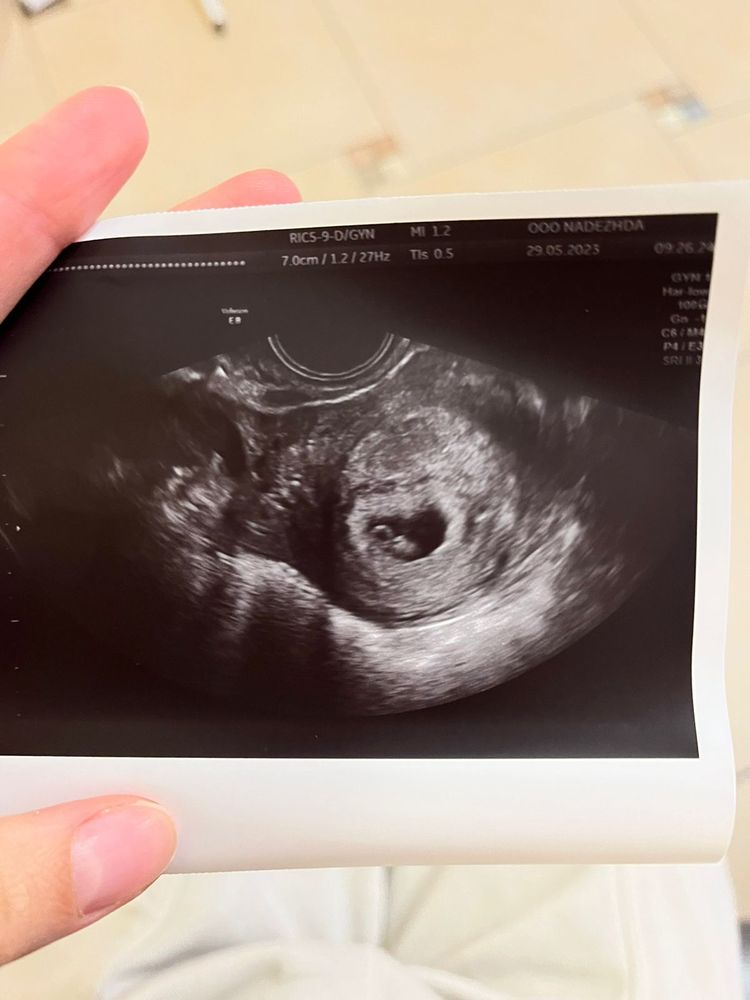

Изображение 7 ровно

Изображение Тут без одного дня 7 недель

Изображение Срок 7 недель, ктр 0.53 см. Соответствует сроку 6 и 2 дня.